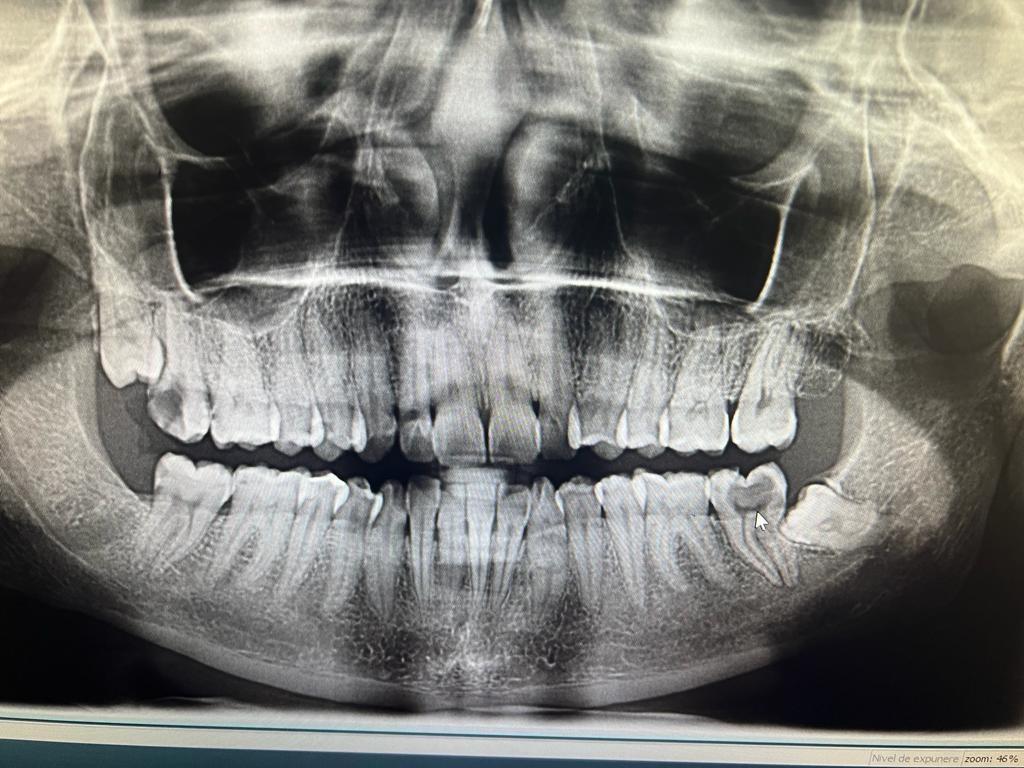

– control radiologic.